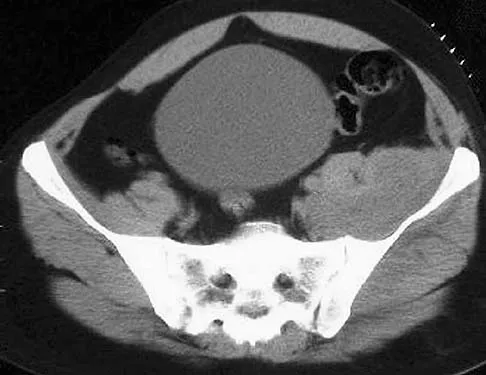

An 18-year-old boy reports increasing pain with weight bearing on his right leg and at night. Examination reveals swelling around the right midcalf. Radiographs and an MRI scan are shown in Figures 13a through 13c, and a biopsy specimen is shown in Figure 13d. What is the preferred treatment?

A 66-year-old man has a high-grade angiosarcoma of the right tibia. A radiograph is shown in Figure 43. Treatment should consist of

A 20-year-old patient has foot pain. A radiograph and T1-weighted MRI scan are shown in Figures 8a and 8b. A biopsy specimen is shown in Figure 8c. Treatment should consist of